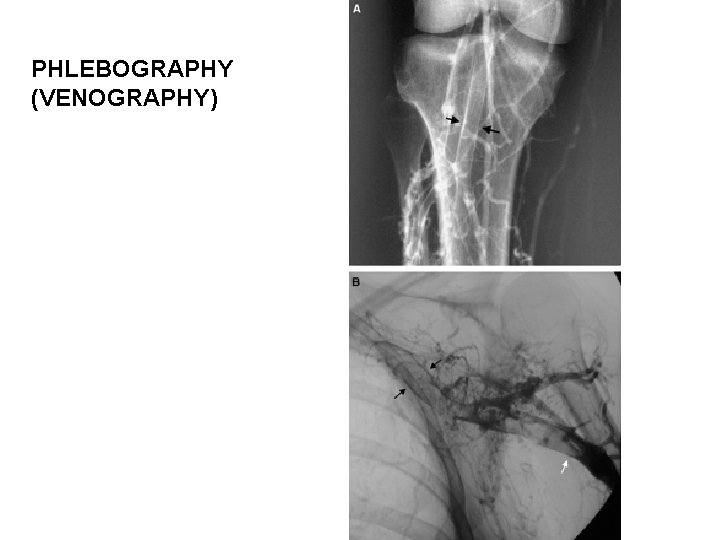

PHLEBOGRAPHY (VENOGRAPHY)